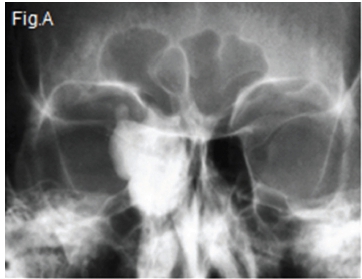

Below are images of the most common tumour of the paranasal sinuses. Discuss the radiographic features discernible and what is your diagnosis?

Upper left (Fig. A) Occipital mental view (caudally angled by 15 degrees) and upper right lateral skull view (Fig. B) shows a large, dense mass occupying the right ethmoid region and expanding into the right orbit. The lower right axial CT (Fig. C) and lower left coronal CT (Fig. D) shows a mass of uniform density in the right ethmoid sinus region. A histological diagnosis of a compact osteoma of the right ethmoid sinus was made.